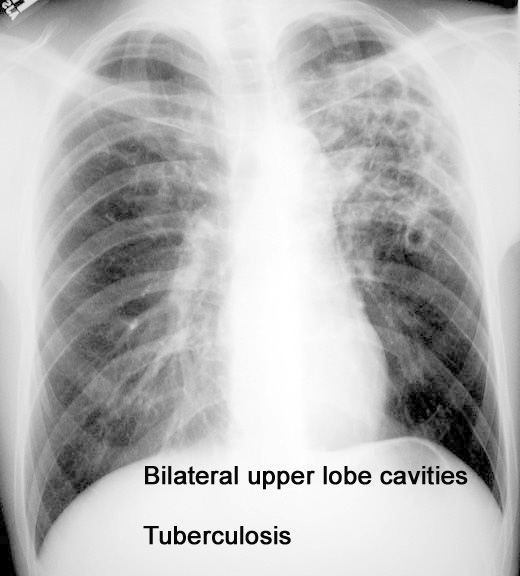

Case 19 Labeled Image What are the causes for bilateral upper lobe cavitary disease?

Case 15 Labeled Image What are the characteristics of tuberculous cavity?